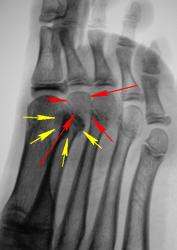

Пациент - подросток был направлен хирургом для рентгенографии переднего отдела стопы. Предварительный диагноз - "Перелом плюсневых костей". Произведено исследование.

Остеоэпифизиолиз  головки 2й плюсневой кости.

А разве это не проекционное наложение тени сесамовидной кости?

Края "сесамовидной" кости выглядят как то с заострением, не характерно для сесамовидной кости, но если осевая положительная вполне возможно переломчик.

На мой взгляд, желтым - сесамовидная кость, красным - интактная головка плюсневой

Весьма убедительно. Но вот как поступить, коллега Вега, если в данном месте резкая локальная боль, ибо пациентку и снимки пациентки смотрели вместе с хирургом. Клинически, как утверждает коллега хирург, и хирург довольно опытный, весьма похоже на перелом?

Конечно, можно через 7 дней сделать контроль, или как?

Если клинически похоже на перелом, то однозначно - гипс с рентгенконтролем через неделю.

Контроль, конечно же, без гипса. Если на втором снимке патологии тоже нет, и клиники нет - гипс выкидываем. Если остается клиника или на снимке все-таки видим перелом - гипс до сращения. Это общепринятая тактика.